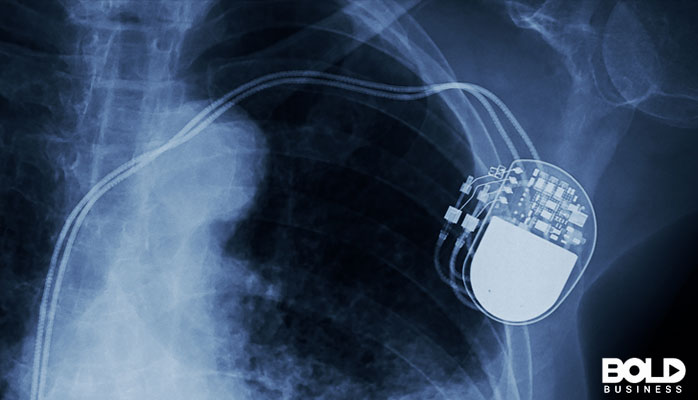

Implanted devices aren’t anything new. For decades, surgeons and physicians have utilized medical implant technology to enhance patient care. But in the past, these types of devices tended to provide therapeutics. Specific implants could improve some conditions while preventing others. Examples of this included pacemakers for cardiac arrythmias and cochlear implants to aid hearing difficulties. But this is rapidly changing as implanted devices are now increasingly focused on health monitoring. And this not only has repercussions for medical providers but for patients as well.

Several medical fields rely on implanted devices to provide better healthcare services to patients. Cardiologists and cardiothoracic surgeons place defibrillators and pacemakers to prevent fatal arrythmias. Neurologists prescribe implanted neurostimulators to reduce painful conditions. Even ophthalmologists use retinal implants to correct vision. But these types of implanted devices differ greatly from the latest medical implant technology. Newer devices are much smaller and boast greater connectivity to programs and mobile applications. And as a result, the potential uses for these newer technologies are much more expansive.